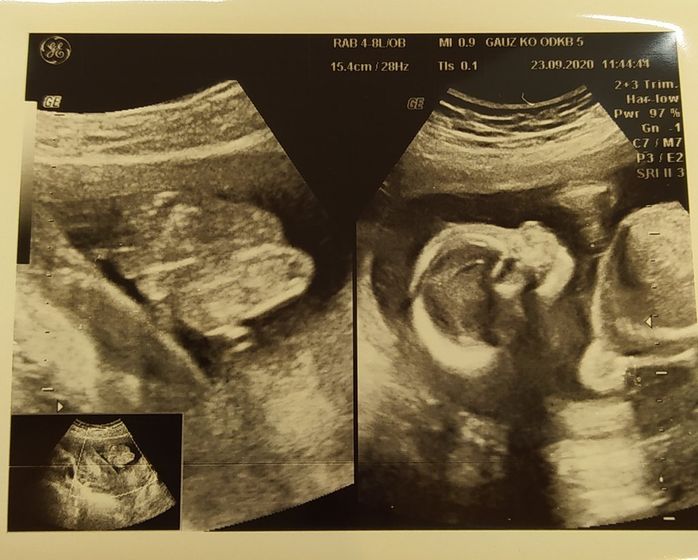

Вот и половина беременности позади ? Сегодня была на скрининге, всё хорошо, развивается малыш отлично, лежитправда пока поперек, вес 327 гр (дочка на этом сроке была 360гр), плацента отлично поднимается уже совсем чуть-чуть край перекрывает, шейка 35мм, узист сказала красивые большие глаза и маленький носик ?ну собственно дочка такая же у нас нос пипка, глазки бусинки))) Живёт в домике мальчик ??я изначально так думала, расскажу немного о приметах, хоть и сама скептически отношусь к этому) Сразу дочку спросили, когда узнали о беременности, кто живет у мамы в животике? она сказала мальчик) во сне 3 раза видела мальчика, не именно что это мой сын, но сны были как бы об этом (я сначала не очень была рада беременности, так как были на то свои причины и один из самых первых снов видела, что иду домой, под ногами уже листва осень и на детской площадке стоит малыш один, на вид около года хорошенький такой, подхожу ближе, а он такой одинокий и в глубине души я понимаю что он не нужен никому… потом проснувшись долго плакала после этого сна, даже сейчас вспоминая сердце щимит, очень просила прощения и приняла эту беременность и говорила, что очень жду его и он очень желанный), ну и ещё из методов по обновлению крови тоже получался мальчик и на последок недавно был пост про гадание с кольцом рад животом тоже показало мальчик))) может всё и совпадения, но очень интересно)) Кстати прибавка 3кг, живот больше уже чем на этом сроке в первую беременность) кому интересно фото в комментариях) а здесь фото слева это две ножки, ну и с права головешка ?уже любим и ждём, муж счастлив, хотя мы были бы рады и девочке, за плечами у нас было 7 лет бесплодия, дочку зачали с помощью стимуляции и эта беременность на 98% была невозможна естественным путем, а она взяла и случилось, видимо так суждено с выше)

С лева беременность дочкой, с права сейчас сыном)